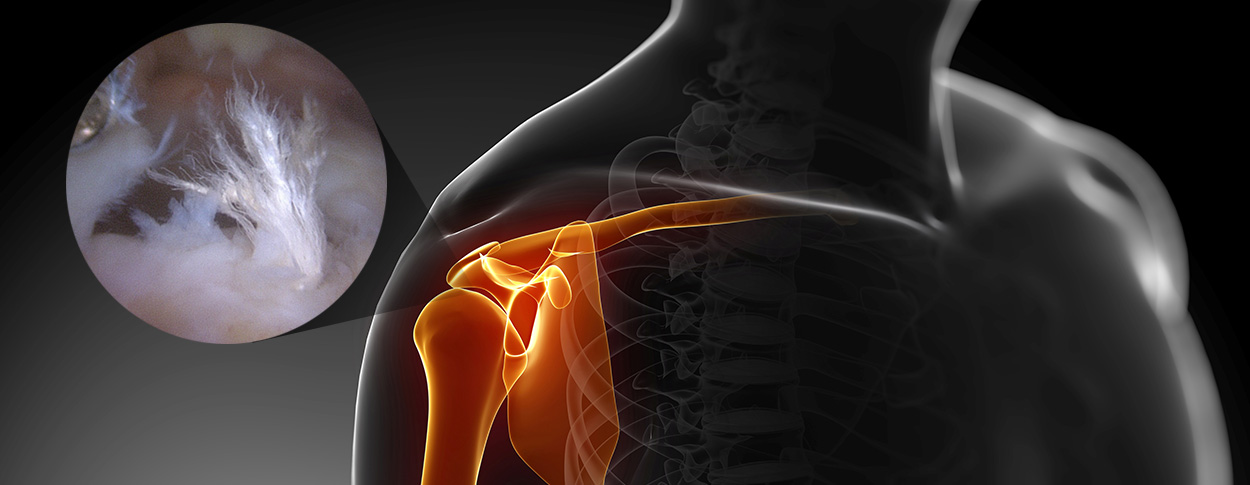

관절내시경은 작은 절개 부위로 고해상도 카메라를 삽입하여 관절 내부를 관찰하는 방법으로

화면을 통해 병변 부위를 직접 확인하면서 손상 정도에 따라 파열된 힘줄을 봉합하거나 염증을 제거할 수 있습니다.